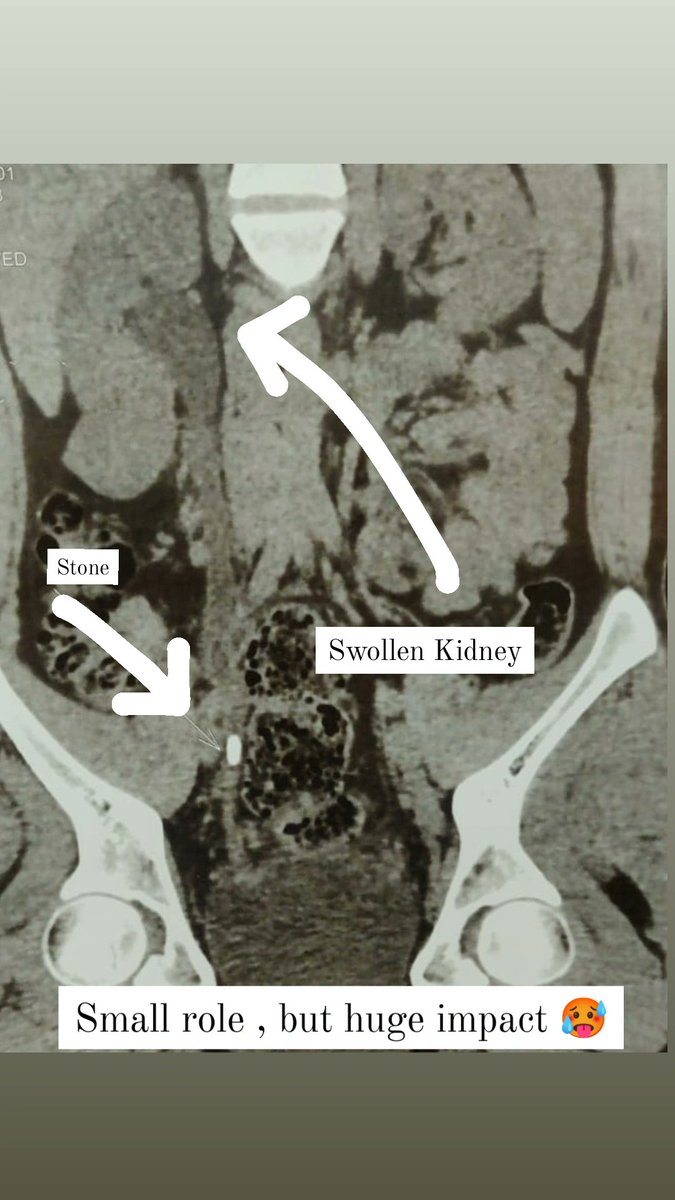

Urologist/Urosurgeon Kidney stones❤️